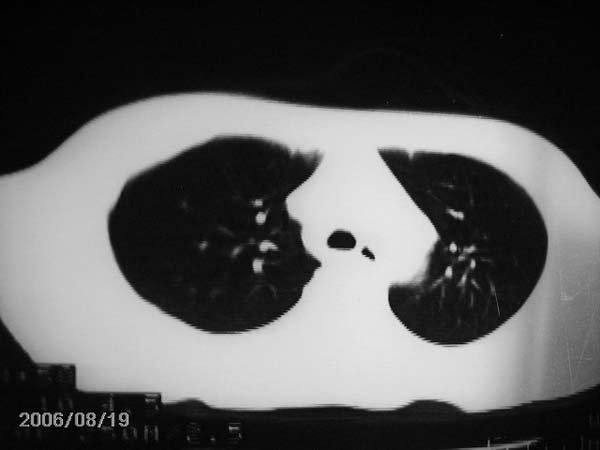

男,13岁,发烧半月,干咳无痰,正规使用抗生素半月,现在仍是午后低烧!!!未做痰检

右中肺呈大片状密度欠均匀影,内见含气支气管.

结合病史,考虑:右中肺大叶性肺炎(吸收期).

右肺中叶大片状密度增高影,内密度不均匀,右肺门处增大,应该是淋巴结肿大,结合临床首先考虑原发性肺结合可能性大,不排除合并感染可能,建议治疗后复查.

灶内密度不均,似乎有囊状,条状影,考虑右中叶综合症; 从照片中看不出有无钙化灶,若明显则考虑结核性。

考虑中叶综合征(右肺门肿大淋巴结伴中叶阻塞性炎症)